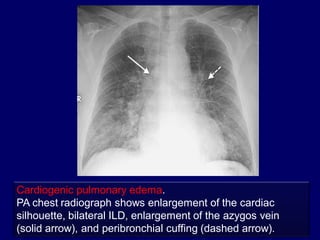

Cardiogenic pulmonary edema.

PA chest radiograph shows enlargement of the cardiac

silhouette, bilateral ILD, enlargement of the azygos vein

(solid arrow), and peribronchial cuffing (dashed arrow).